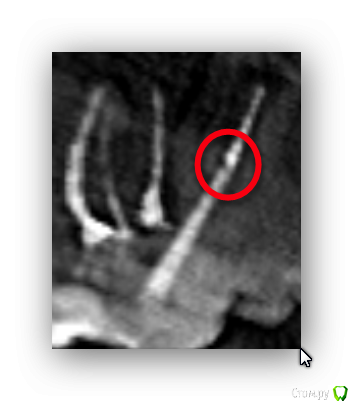

freeman22 Опубликовано 27 октября, 2015 Поделиться Опубликовано 27 октября, 2015 (изменено) Здравствуйте.В зубе установлен. Нет ли перелома корня зуба? Изменено 27 октября, 2015 пользователем freeman22 Ссылка на комментарий

DmitrySH Опубликовано 27 октября, 2015 Поделиться Опубликовано 27 октября, 2015 Это граница между штифтом и пломбировочным материалом. Цемент возможно не рентгенконтрастный. Ссылка на комментарий